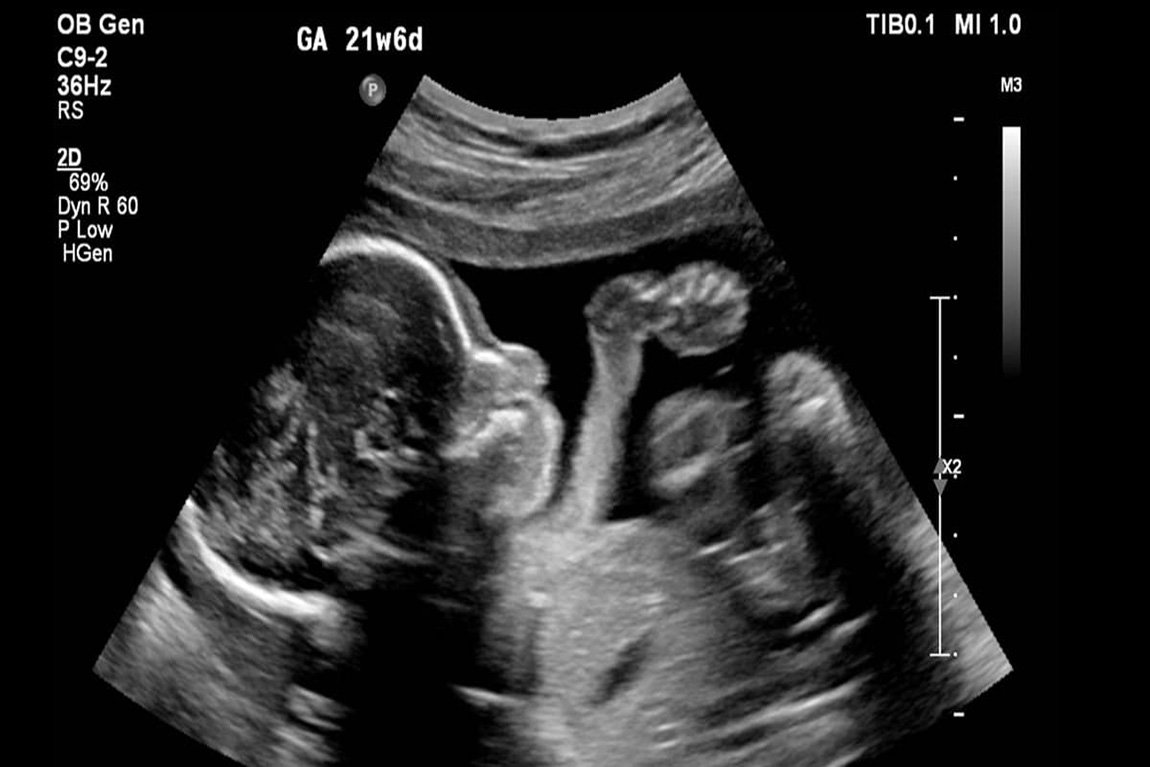

وی گفت: برای بعضی بیماریها مثل سندروم داون جنجال ایجاد میشود که نمونهی اینها را برای غربالگری به خارج از کشور میفرستند، در صورتی که اصلا اینطور نیست، چون نمونه آن در داخل کشور غربالگری میشود، گرچه الان تحریم هستیم و کیفیت دستگاه و تجهیزات و کیت برای این آزمایش تحت تاثیر قرار میگیرد.

وی با بیان اینکه دو نوع کنترل داریم، ادامه داد: یک نوع، قبل از اینکه کودک به دنیا بیاید، بیماری در وضعیت جنینی مستقر میشود و ما میتوانیم قبل از عروج روح آن را شناسایی کنیم، نوع دیگر زمانی است که کودک سالم به دنیا میآید و اگر شناسایی نشود بیماری شروع میشود، اما وقتی بیماری در جنین است باید بیماری در زمان جنینی شناسایی شود، چون یک بخشی از بیماریها در آن زمان قابل درمان است و بخش دیگر هم با شرایط خاص قابل پیشگیری خواهد بود.

سماوات گفت: برای برخی بیماریها که قابل درمان نیست، ما به مادر قبل از ولوج روح فقط پیشنهاد سقط میدهیم، که مادر تصمیم میگیرد، گاهی مادر قصد دارد بچه را بزرگ کند و آن زمان ما هر حمایتی که نیاز است را برای او انجام میدهیم.

وی ادامه داد: اگر شناسایی درستی صورت نگیرد، جنینهای ناقص الخلقه افزایش پیدا میکنند، اینها جمعیت را افزایش نخواهند داد، چون اکثرا درگیر مرگ زودرس میشوند، بسیاری از آنها زیر ۵ سال فوت میکنند، این کودکان جدا از اینکه خیلی زجر میکشند، باعث ایجاد مشکلات زیادی برای مادر و خانوادهی خودشان هم میشوند.

سماوات در پایان با تاکید بر اینکه چنین اتفاقاتی میتواند بر افسردگی و بر هم خوردن نهاد خانواه اثر داشته باشد، گفت: با این نوع زایمانها که احتمال به دنیا آمدن کودک بیمار را زیاد میکند، خانواده و حتی خویشاوندان دیگر دچار ترس از بچه دار شدن میشوند و از حاملگی امتناع میکنند، ما در سال حدود ۷۰ هزار تولد نوزاد با ناهنجاریهای شدید داریم که فقط نصف اینها قابل مداخله و شناسایی است، تا الان با غربالگریها حدود ۸ هزار نفر از آنها را توانستیم شناسایی کنیم، اگر غربالگریها گسترش پیدا کند تا ۳۰ هزار نفر از آنها قابل شناسایی است و ممکن است به دلیل افزایش امکانات بیشتر هم شود و اگر نتوانیم غربالگریها را انجام دهیم به مرور تا ۷۰ هزار ناهنجاری گریبان مردم را خواهد گرفت.